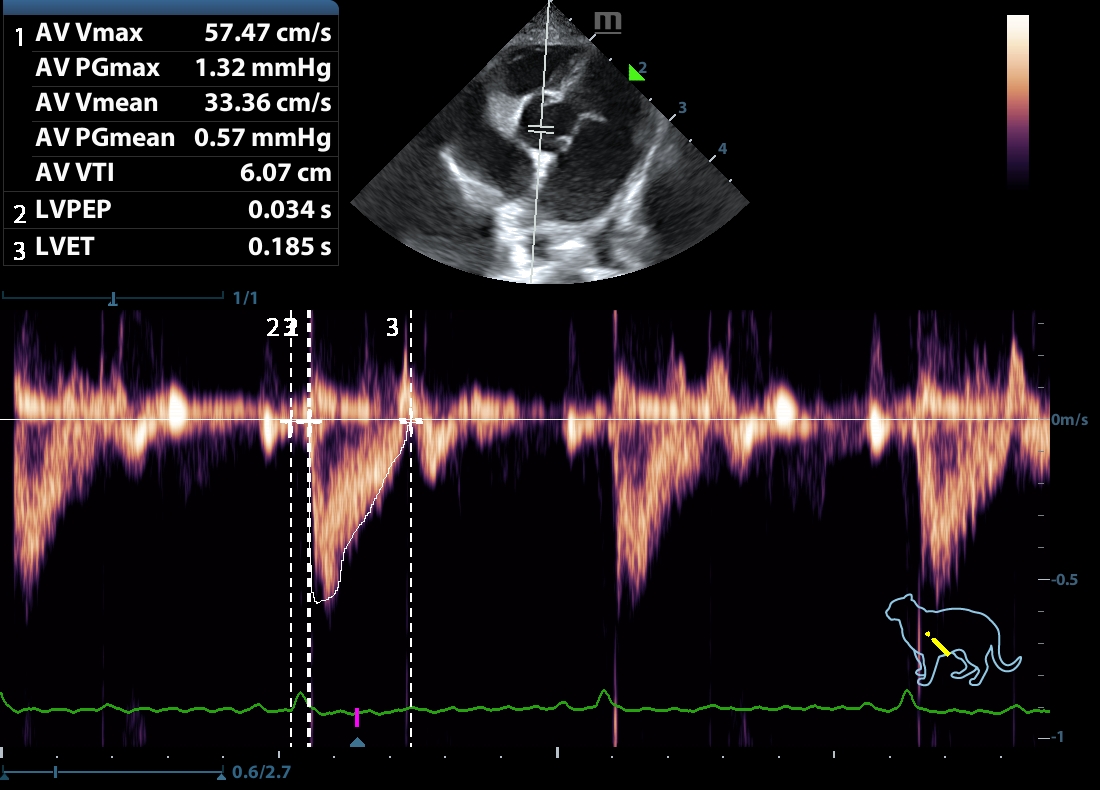

202507112253250161CARD.JPG